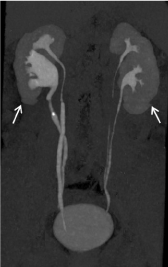

Qualitative evaluation: (Figures 5, 6)

Figure 5. Qualitative evaluation

Figure 5a. Excretory WV mode –sagittal view –result of the automatic stitching (a1). The junctions between volumes are recognized at certain levels (→ white arrow); after additional manual stitching (a2); the junctional zones have disappeared.

Figure 5b. Qualitative evaluation between helical acquisition unenhanced (b1) and excretory WV mode (b2). There is no visual difference for a clinical purpose between those two acquisition modes.

Figure 6. Clinical cases

Figure 6a. Normal patient (follow up after ablation of a bladder excretory tumour)-antero posterior MIP projection. The ureters are entirely evaluated without disruption.

Figure 6b. Duplicated excretory system with a urinary stone in the upper part of the lower excretory system. The ureter above the stone is collapsed due to the pathological process. Note that there is a discontinuity (↑ white arrow) of the lower pole of the kidneys, but it does not interfere for the right diagnosis.

Agreement between the two readers was excellent with a k correlation coefficient as high as 0.89. The intervention of the third reader was required in 2 cases. For image quality, our results according the subjective scale were as follows: score 1: poor (no case), score 2: fair (no case), score 3: good (14 cases) and score 4: excellent (31cases).

Concerning the quality of the stitching based on the continuity of the ureter, it was found discrepancies between the different volumes. We have found between the first and second volume at the upper level of the abdominopelvic region the following results: 82%,15% and 3% of cases for point 1, 2 and 3, respectively. For the three lower volumes, the final stitching was always excellent and rated 1 in 44 cases (except in one case with point 2).) No cases were uninterpretable. The diagnosis was performed without any ambiguity.